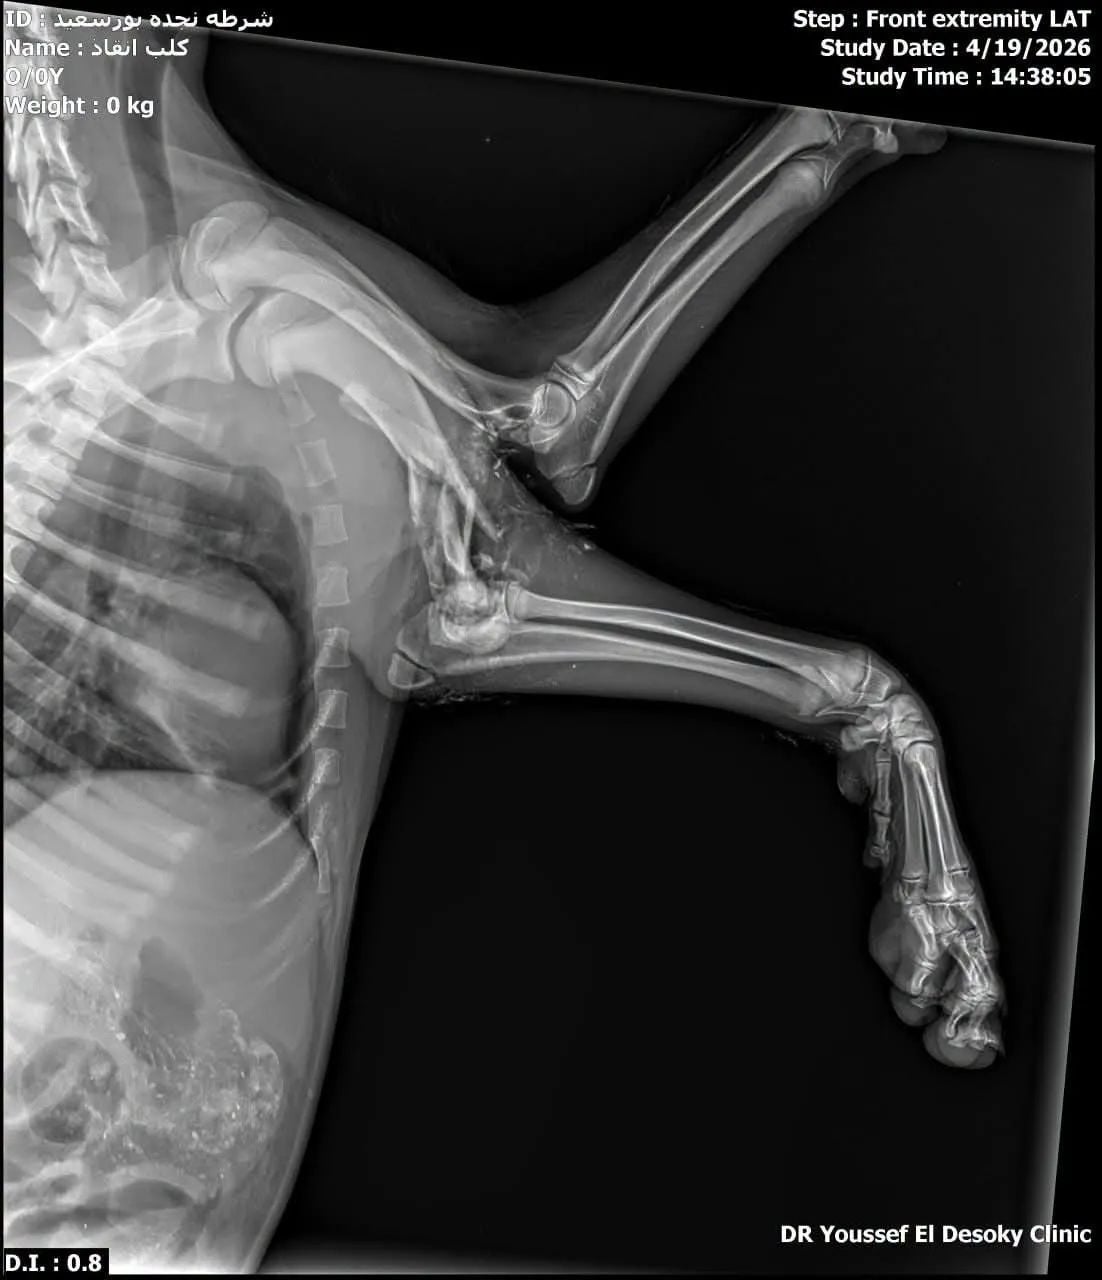

وأكد الدكتور طارق فرنسيس مدير عام مديرية الطب البيطري ببورسعيد، أنه بالفعل تم استلام الكلب المصاب وهناك فريق طبي من الأطباء بشلتر جنوب بورسعيد يقوم على التعامل مع إصابته .

وأشار في تصريح خاص لـ “اليوم السابع”، إلى أن الكلب أصيب بكسر وجرح قطعى، ويتم التعامل السريع معه، بغرفة عمليات الشلتر وبعدها سيتم رعايته حتى تتحسن حالته الصحية.

واستقبل الدكتور محمد عيسى مدير المستشفى البيطري والمسؤول الطبي عن شلتر بورسعيد، حالة الكلب لاستكمال العلاج داخل الشلتر، بعد وصول السيارة الخاصة بها لنقل الكلب المصاب إلى شلتر بورسعيد.